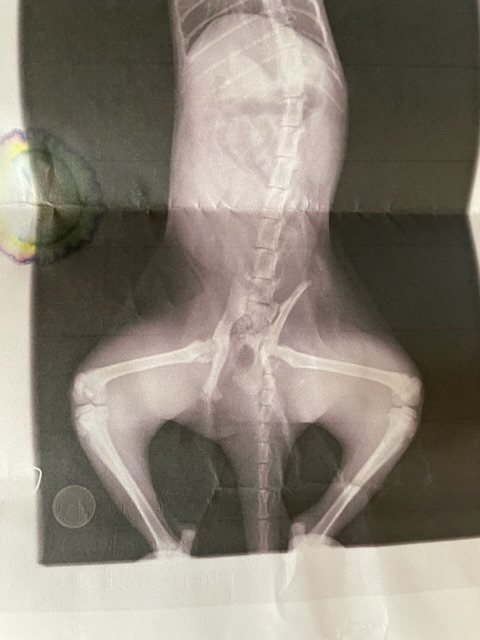

さくらが、前足2本で体を引きずって部屋の裏に助けを求めに来ました、私の気持ちとして、これはおかしいと思い助けないといけないと思いました。一軒目の獣医に行った時、レントゲンだけを取り骨盤骨折と分かりました。

「うちでは無理だから紹介します」と南松本ペットクリニックを紹介されました。

南松本ペットクリニックでも、骨盤骨折と片方の足大腿骨骨折していて当たらないように痛みを取るため削るそうです、また骨盤骨折が治ってからシッポを噛むようなら、しっぽの骨が離れているため、切断しないといけないと言われました。

(動物病院より掲載許諾をいただいております。)

骨折整復手術を行います。いただいた支援金は、治療費、その後の飼育費とします。

野良猫の子猫の桜が、突然、アパートの裏に前足二本で体を引きずって助けを求めに来ました、南松本、ペットクリニックに連れて行ったら骨盤骨折、右足大腿骨骨折、しっぽの骨が離れていて何とか直して飼ってあげたいです。骨折整復手術を行います。支援金は、治療費、その後の飼育のための費用とします。桜を元気にしてあげたく、皆様のご協力お願いいお願します。